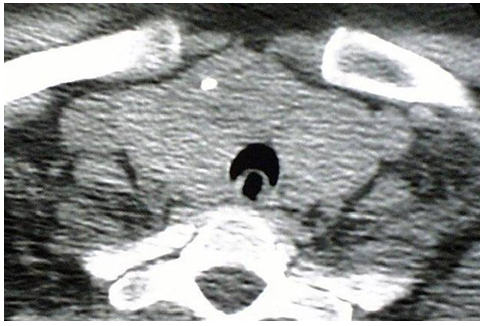

Figure 4. Pre-operative CT scan of the neck demonstrating crescent trachea sign